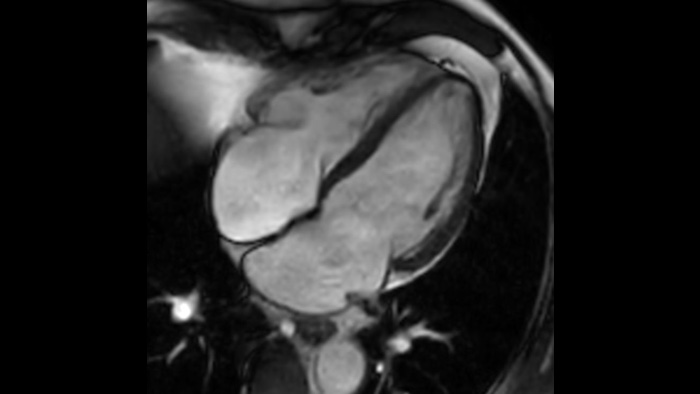

Діагностична точність Розширте свої можливості візуалізації в усіх клінічних областях. Дізнайтеся, які переваги отримують ваші колеги.

Швидкість і& комфорт Зниження необхідності затримки дихання на 40% без втрати якості зображення4.

Дізнайтеся, як інституту MCVI вдалося покращити якість МРТ-досліджень.